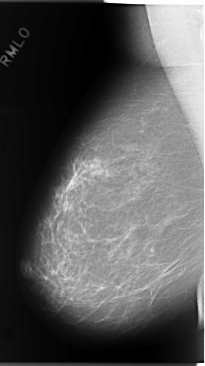

C_0106_1.RIGHT_MLO

RIGHT_CC LINES 5944 PIXELS_PER_LINE 3240 BITS_PER_PIXEL 12 RESOLUTION 50 NON_OVERLAY

RIGHT_MLO LINES 5848 PIXELS_PER_LINE 3280 BITS_PER_PIXEL 12 RESOLUTION 50 NON_OVERLAY